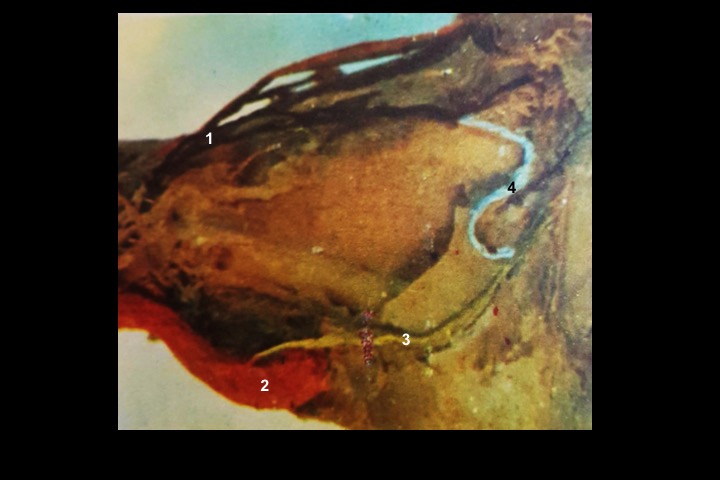

Preparação anatômica da órbita_2